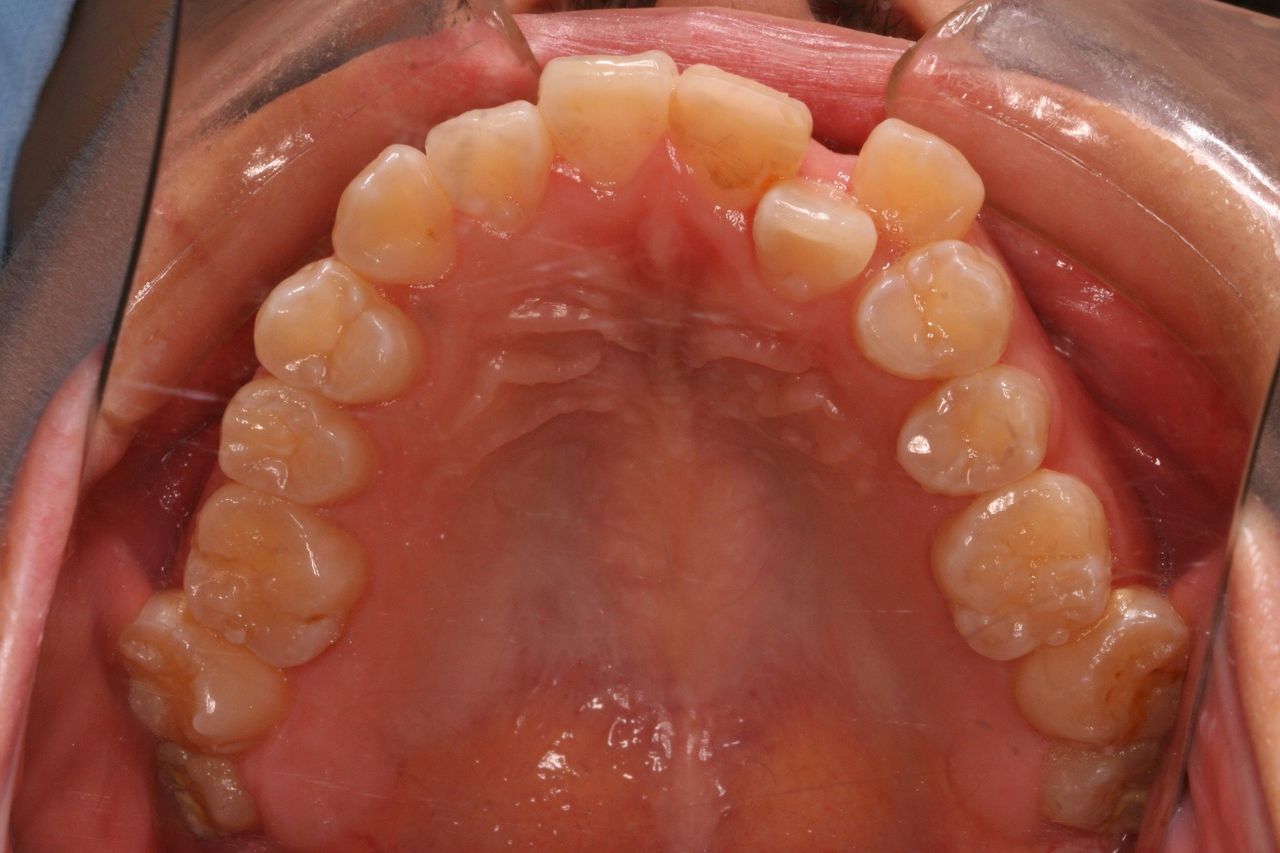

治療終了時です。

初診の状態と比較していただければ、仕上がりの状態がより理解できると思います。